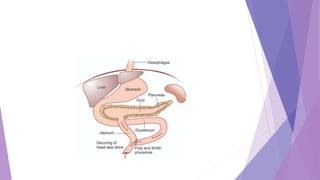

Pancreatic Duct Dilation Secondary to

Duct Stones or Strictures

95% subtotal pancreatectomy.

 Distal pancreatectomy—Spleen, body and tail of the pancreas are removed—

Child’s operation.

 Puestow’s operation—As the duct is dilated more than 8 mm, duct can easily

be opened longitudinally. After removing all stones from the duct, it is

anastomosed to the jejunum as side to side Roux-en-Y anastomosis. In

Puestow’s operation spleen is removed.

 The anterior surface of the pancreatic duct is opened

 After all stones are removed, a standard Roux-en-Y is used to create a two-

layer lateral pancreaticojejunostomy.

 The modified Puestow procedure provides palliation of pain in 80% of cases

 Puestow and Gillesby's longitudinal pancreaticojejunostomy

Surgery

 Longitudinal pancreatico-jejunostomy after excision of peripancreatic duct tissue—here superficial

part of the head of pancreas is removed to achieve improved drainage—Frey procedure.

 It is done when ductal dilatation is not adequate; head is more than 4 cm thick. Head coring is done

with retaining 5 mm thick tissue in front of veins, close to duodenum. It shows 75% pain relief in 3

years.

 Also an alternative for patients with a dilated pancreatic duct secondary to a benign stricture in the

head of the pancreas associated with severe inflammation, scarring, or portal hypertension

surrounding the head of the pancreas

 Resection of tail of pancreas with retrograde pancreatico-jejunostomy—Duval procedure.

Frey procedure - intraoperative photographs

Drainage procedures

 Duval’s caudal pancreaticojejunostomy